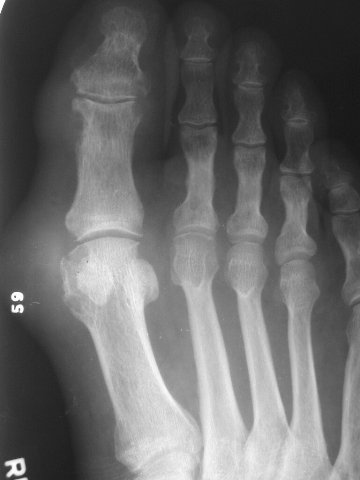

gout foot

Gout